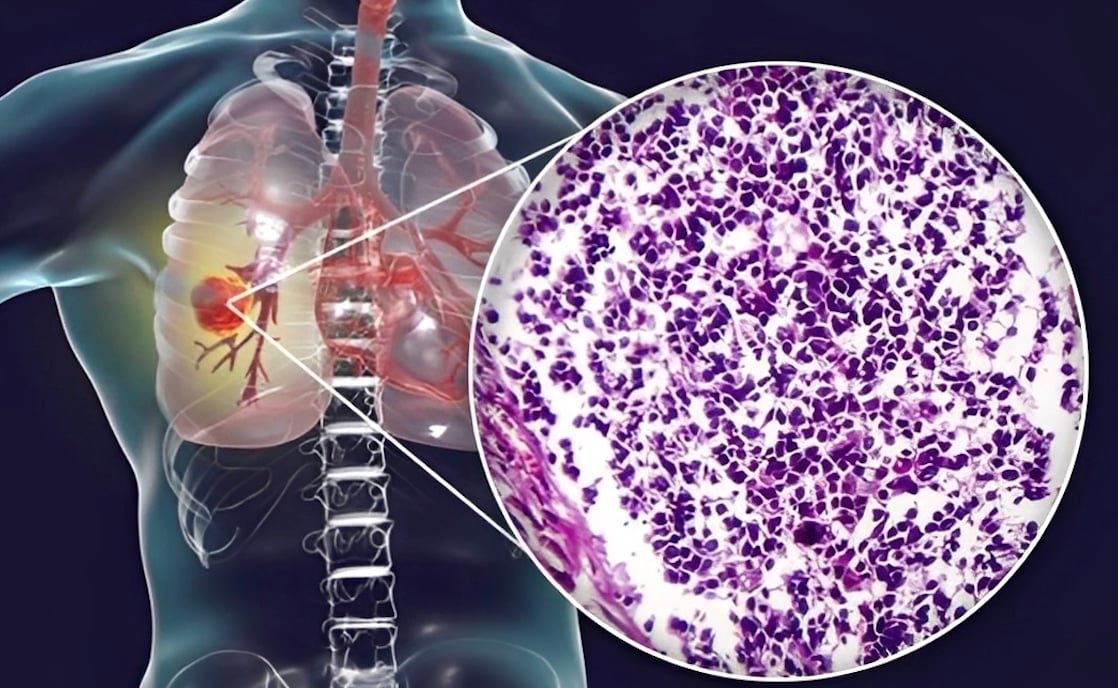

Ο καρκίνος του πνεύμονα παραμένει η πιο συχνή και θανατηφόρα μορφή καρκίνου παγκοσμίως. Αν και το κάπνισμα αποτελεί κυρίαρχο παράγοντα κινδύνου, οι αναδυόμενες έρευνες δείχνουν ότι η διατροφή μπορεί επίσης να διαδραματίσει κρίσιμο ρόλο στην ανάπτυξη της νόσου.

Κατά τη διάρκεια μιας μέσης περιόδου παρακολούθησης 12 ετών, οι ερευνητές κατέγραψαν 1.706 περιπτώσεις καρκίνου του πνεύμονα, συμπεριλαμβανομένων 1.473 μη μικροκυτταρικών και 233 μικροκυτταρικών περιστατικών.

Τα αποτελέσματα της έρευνας έδειξαν ξεκάθαρα ότι οι συμμετέχοντες που κατανάλωναν τις υψηλότερες ποσότητες UPF είχαν σημαντικά υψηλότερη συχνότητα εμφάνισης καρκίνου του πνεύμονα σε σύγκριση με εκείνους που κατανάλωναν τις λιγότερες (495 περιπτώσεις έναντι 331 περιπτώσεων από συγκρίσιμες ομάδες συμμετεχόντων).

- 41% περισσότερες πιθανότητες να αναπτύξουν καρκίνο του πνεύμονα συνολικά

- 37% περισσότερες πιθανότητες διάγνωσης μη μικροκυτταρικού καρκίνου πνεύμονα

- 44% περισσότερες πιθανότητες διάγνωσης μικροκυτταρικού καρκίνου πνεύμονα